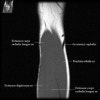

- Sagittal section

1) Biceps Brachii tendon and Brachiallis muscles

2) Radial head for radiographically occult fractures

3) Distal Triceps tendon